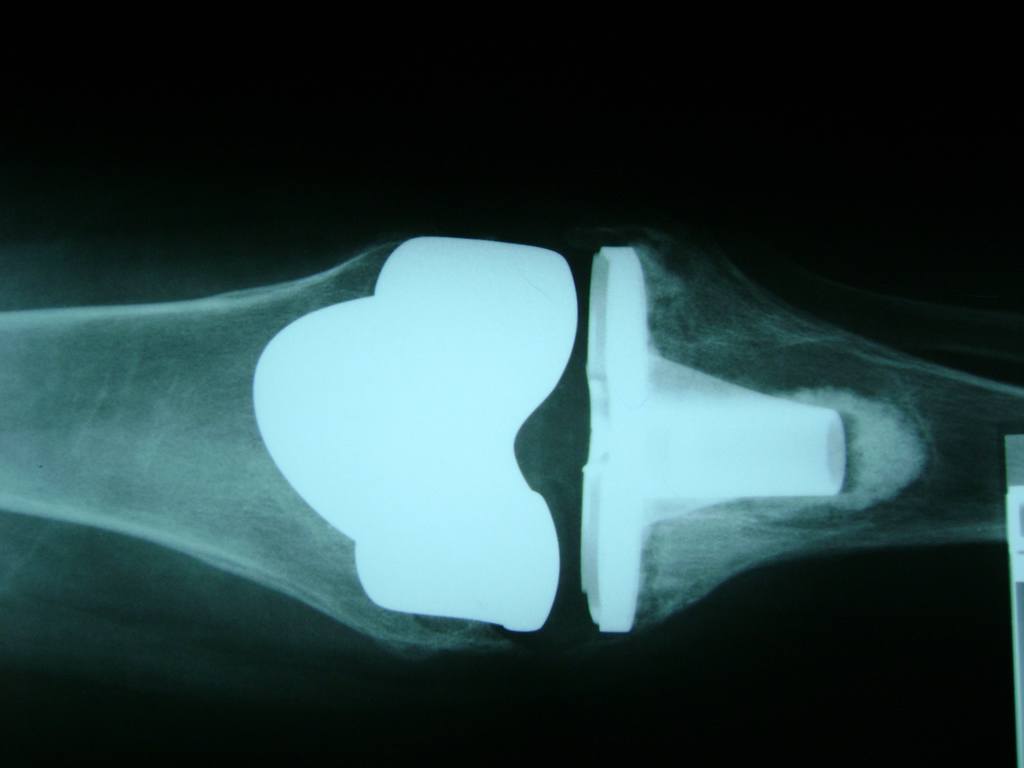

La artroscopia de rodilla es un cirugía en el cual la estructura interna de la articulación es examinada ya sea para realizar un diagnostico o para realizar un tratamiento, este procedimiento se realiza utilizando un instrumento parecido a un pequeño tubo llamado artroscopio.

La artroscopia se popularizo en 1960 y hoy en día es muy común en todo el mundo. Típicamente, es realizada por cirujanos ortopédicos de manera ambulatoria. Cuando se realiza de manera ambulatoria los pacientes pueden regresar a casa después de la operación, no se requiere quedarse en hospital.